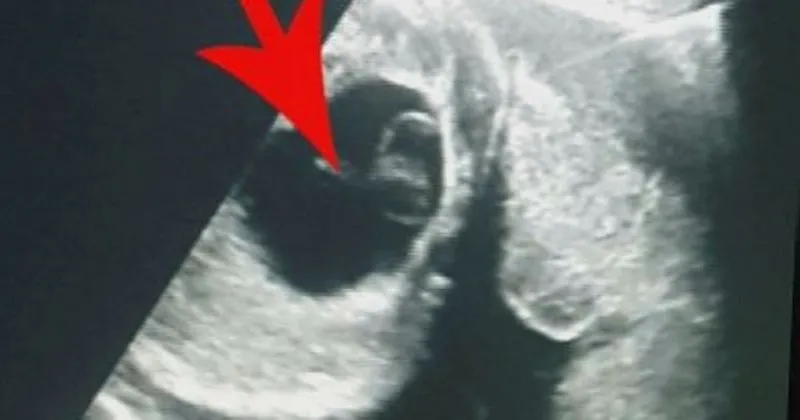

Yumurtalık kisti yumurtalıkların içerisinde ki sıvı dolu keseciklerdir. Bir kadının adet döngüsü sırasında bir yumurta folikül denilen bir kese içinde büyür. Kadin hayattir duygu özel tapan bölüm 61 part 3 konuk. Yumurtalık kistleri çocuk doğurma çağındaki kadınlarda oldukça sık görülür.

Ancak folikül kırılmazsa folikül içindeki sıvı yumurtalık üzerinde kist oluşturabilir. Polistik over sendromu hastaları. Yumurtalık kisti her yaşta kadının yaşayabileceği. Bir kadın bir veya birçok kist geliştirebilir.